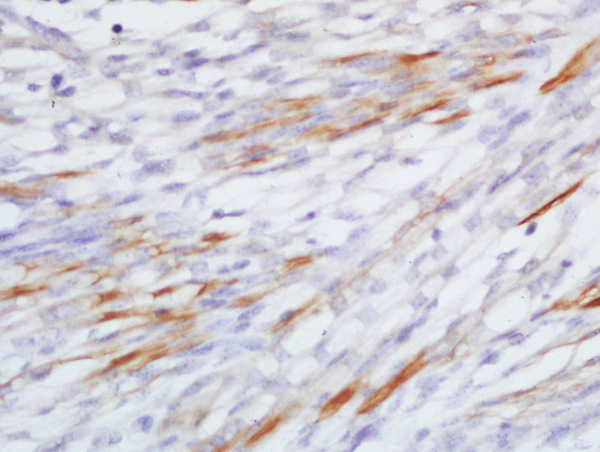

Paraformaldehyde-fixed, paraffin embedded human liver carcinoma; Antigen retrieval by boiling in sodium citrate buffer (pH6.0) for 15min; Block endogenous peroxidase by 3% hydrogen peroxide for 20 minutes; Blocking buffer (normal goat serum) at 37°C for 30min; Antibody incubation with CCL20 Polyclonal Antibody, Unconjugated (bs-1268R) at 1:400 overnight at 4°C, followed by a conjugated secondary for 20 minutes and DAB staining.